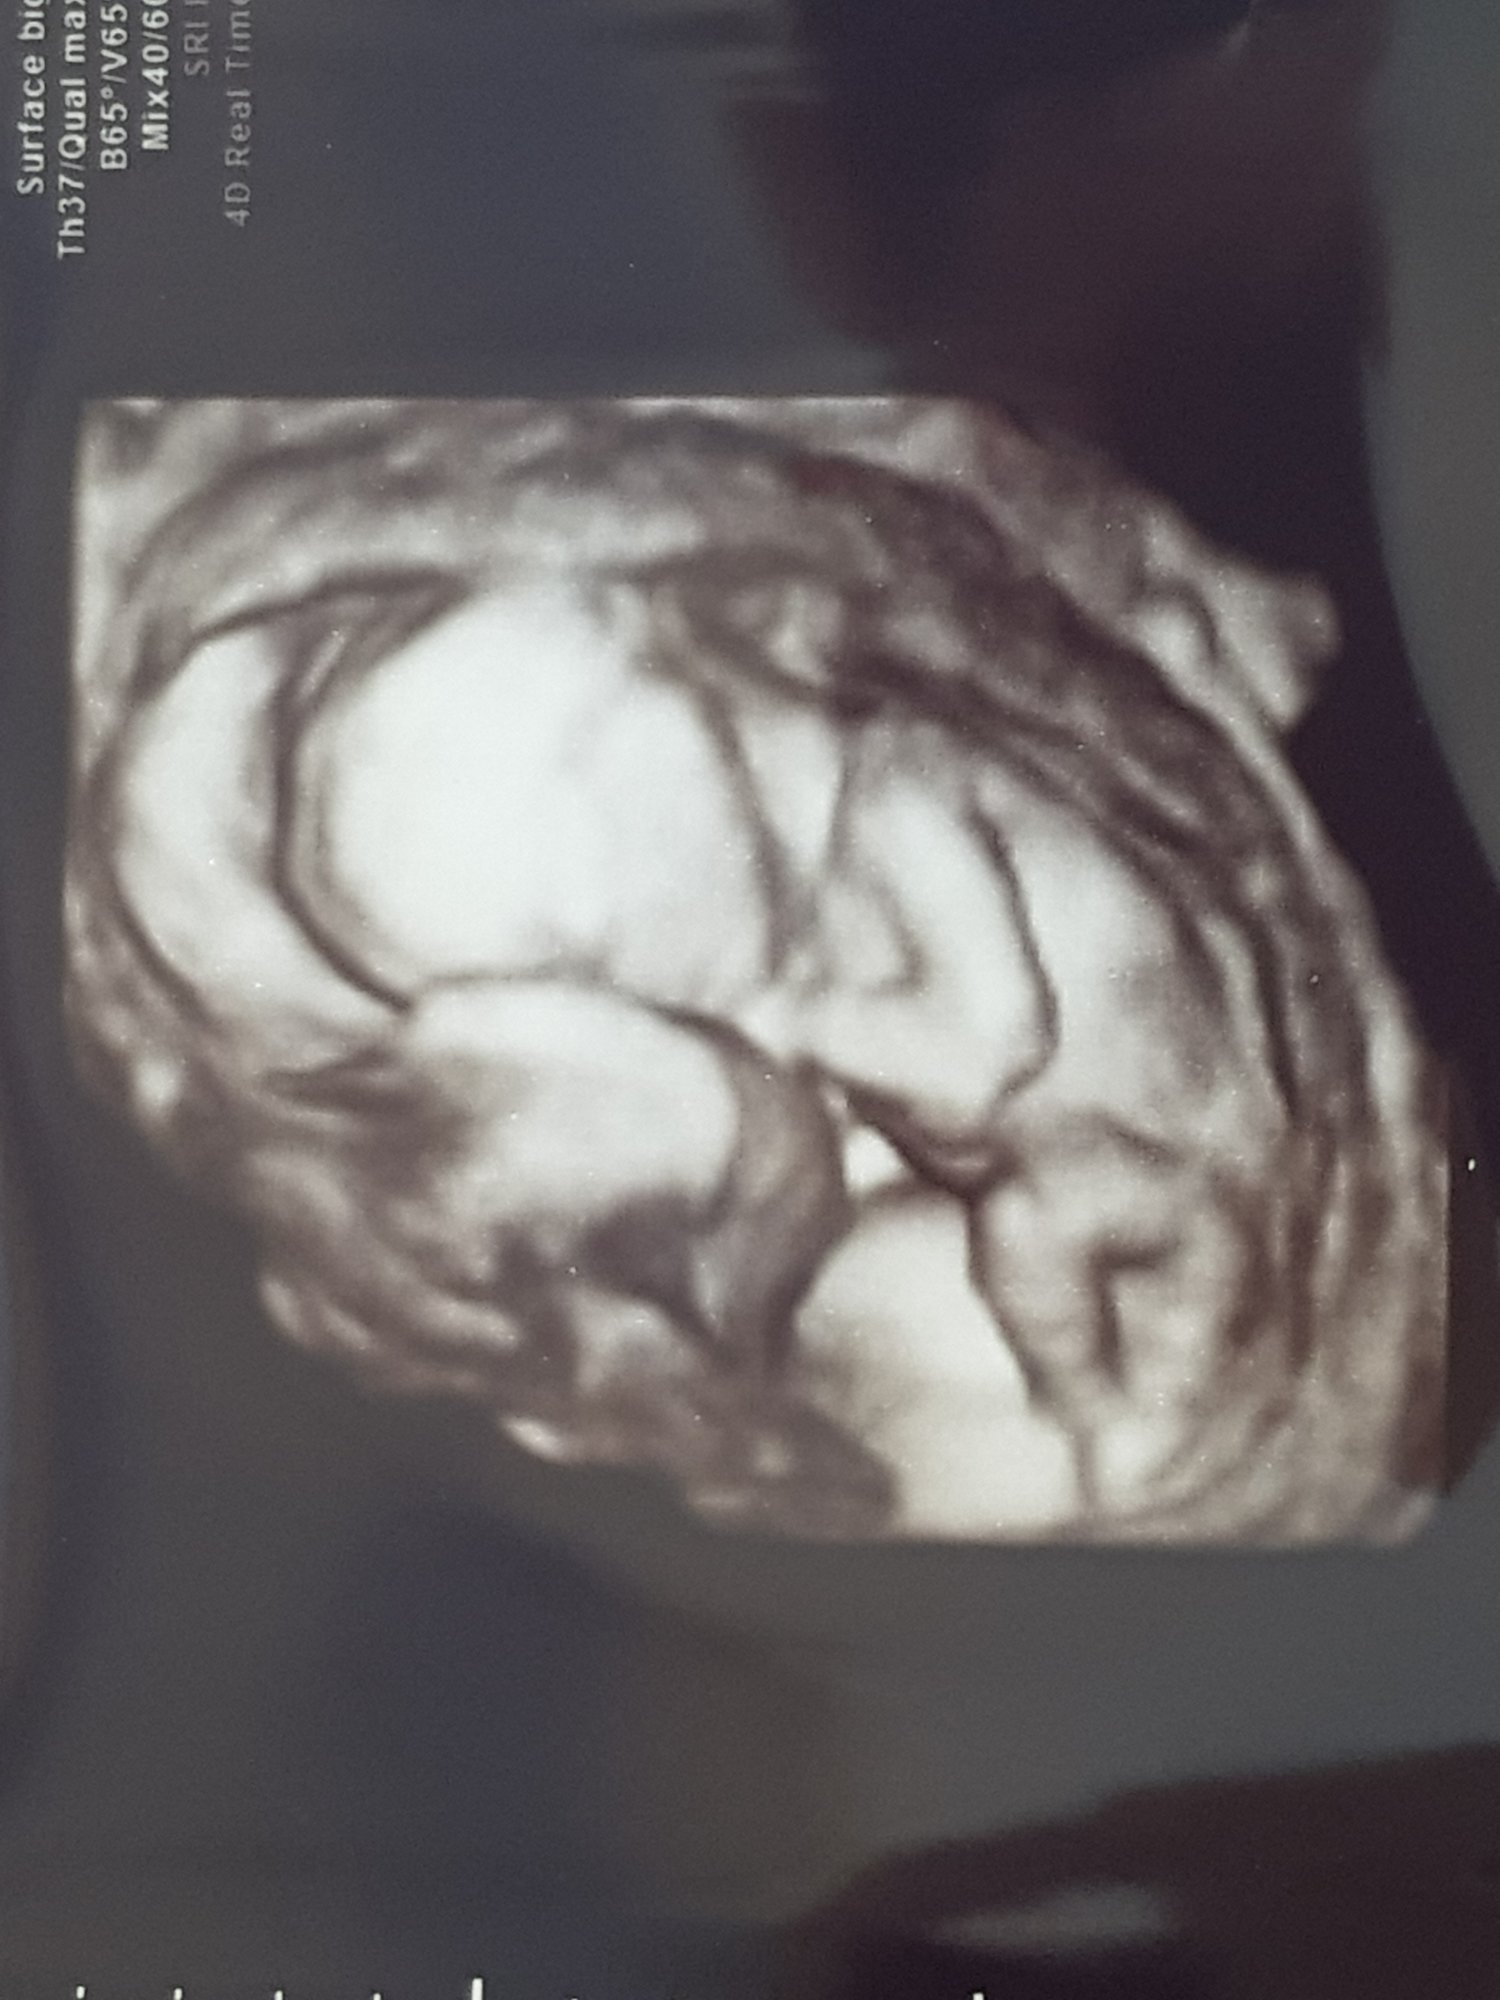

We had our first ultrasound at 10 weeks (I am 12 weeks now - due date at 11/19/18 - which is 3 days before my husband’s bday lol) I am a FTM, and thought this was so incredible. Seeing everything clearly definitely settled my nerves - the baby’s heart was fluttering at 154BPM and moving around like crazy! Our ultrasound tech showed us that she thinks it’s already a boy (my husband was THRILLED lol!) but we are waiting until W20 to confirm and before we start purchasing for the nursery. Now we can finally announce!